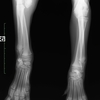

レントゲン検査にて、尺骨成長板の早期閉鎖が認められました。

これにより、橈骨と尺骨長の不均衡が生じ肘関節腔の拡大を伴う事で破行が生じたものと思われます。

術後のレントゲンです。

橈骨の湾曲も改善され、破行も改善し認められなくなりました。